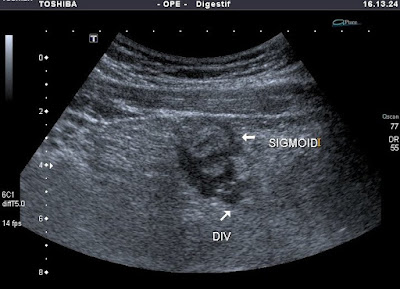

Megvastagodott sigmafal

- Diverticulitis

- Sigmoiditis